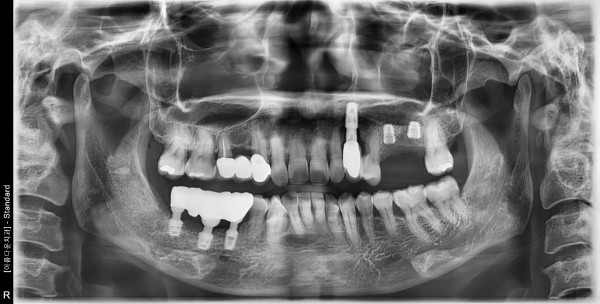

53세 여자 상악 좌측 구치부 발치, 치조골이식술 후 임플란트 식립